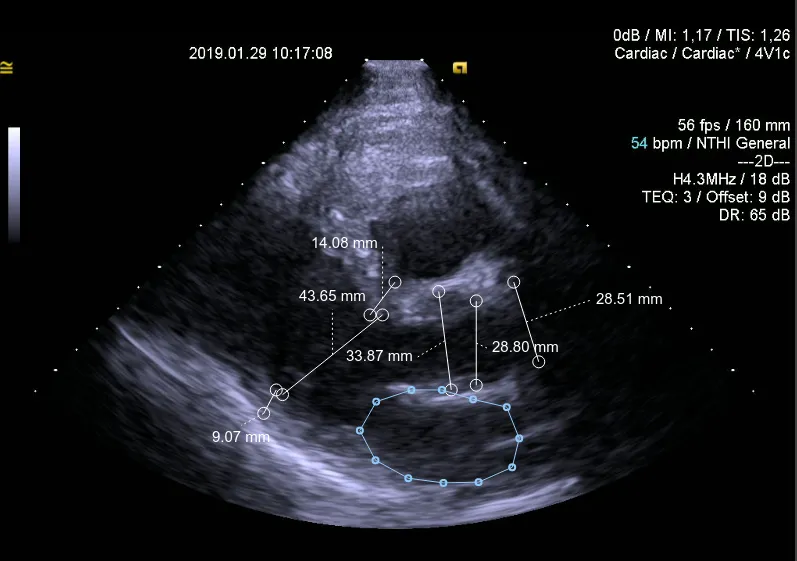

The Ligence team uses deep learning algorithms for creating a tool aimed to simplify echocardiography analysis. They are already the winners of multiple startup contests, including the online Silicon Valley competition. A strong medical background allows the team to work on the solution beneficial for cardiologists worldwide.

Our CEO, Arnas Karužas, is a cardiologist and performs ultrasound examinations of hearts daily. He saw the potential of the tool for automating and simplifying echocardiography analysis and discussed it with Karolis Šablauskas (currently CTO at Ligence) who is a medical doctor as well and has much experience in deep learning.

The idea turned into the implementation — they started from the validation of medical images with deep learning algorithms. The results appeared to be feasible to produce the AI tool for cardiologists.

Specifically, our AI solution provides high performance and accuracy of the examination results. Anyway, a professional specialist is always a 100% gold standard. AI tech is meant to diminish inter-operator variability and reach impressively high accuracy.